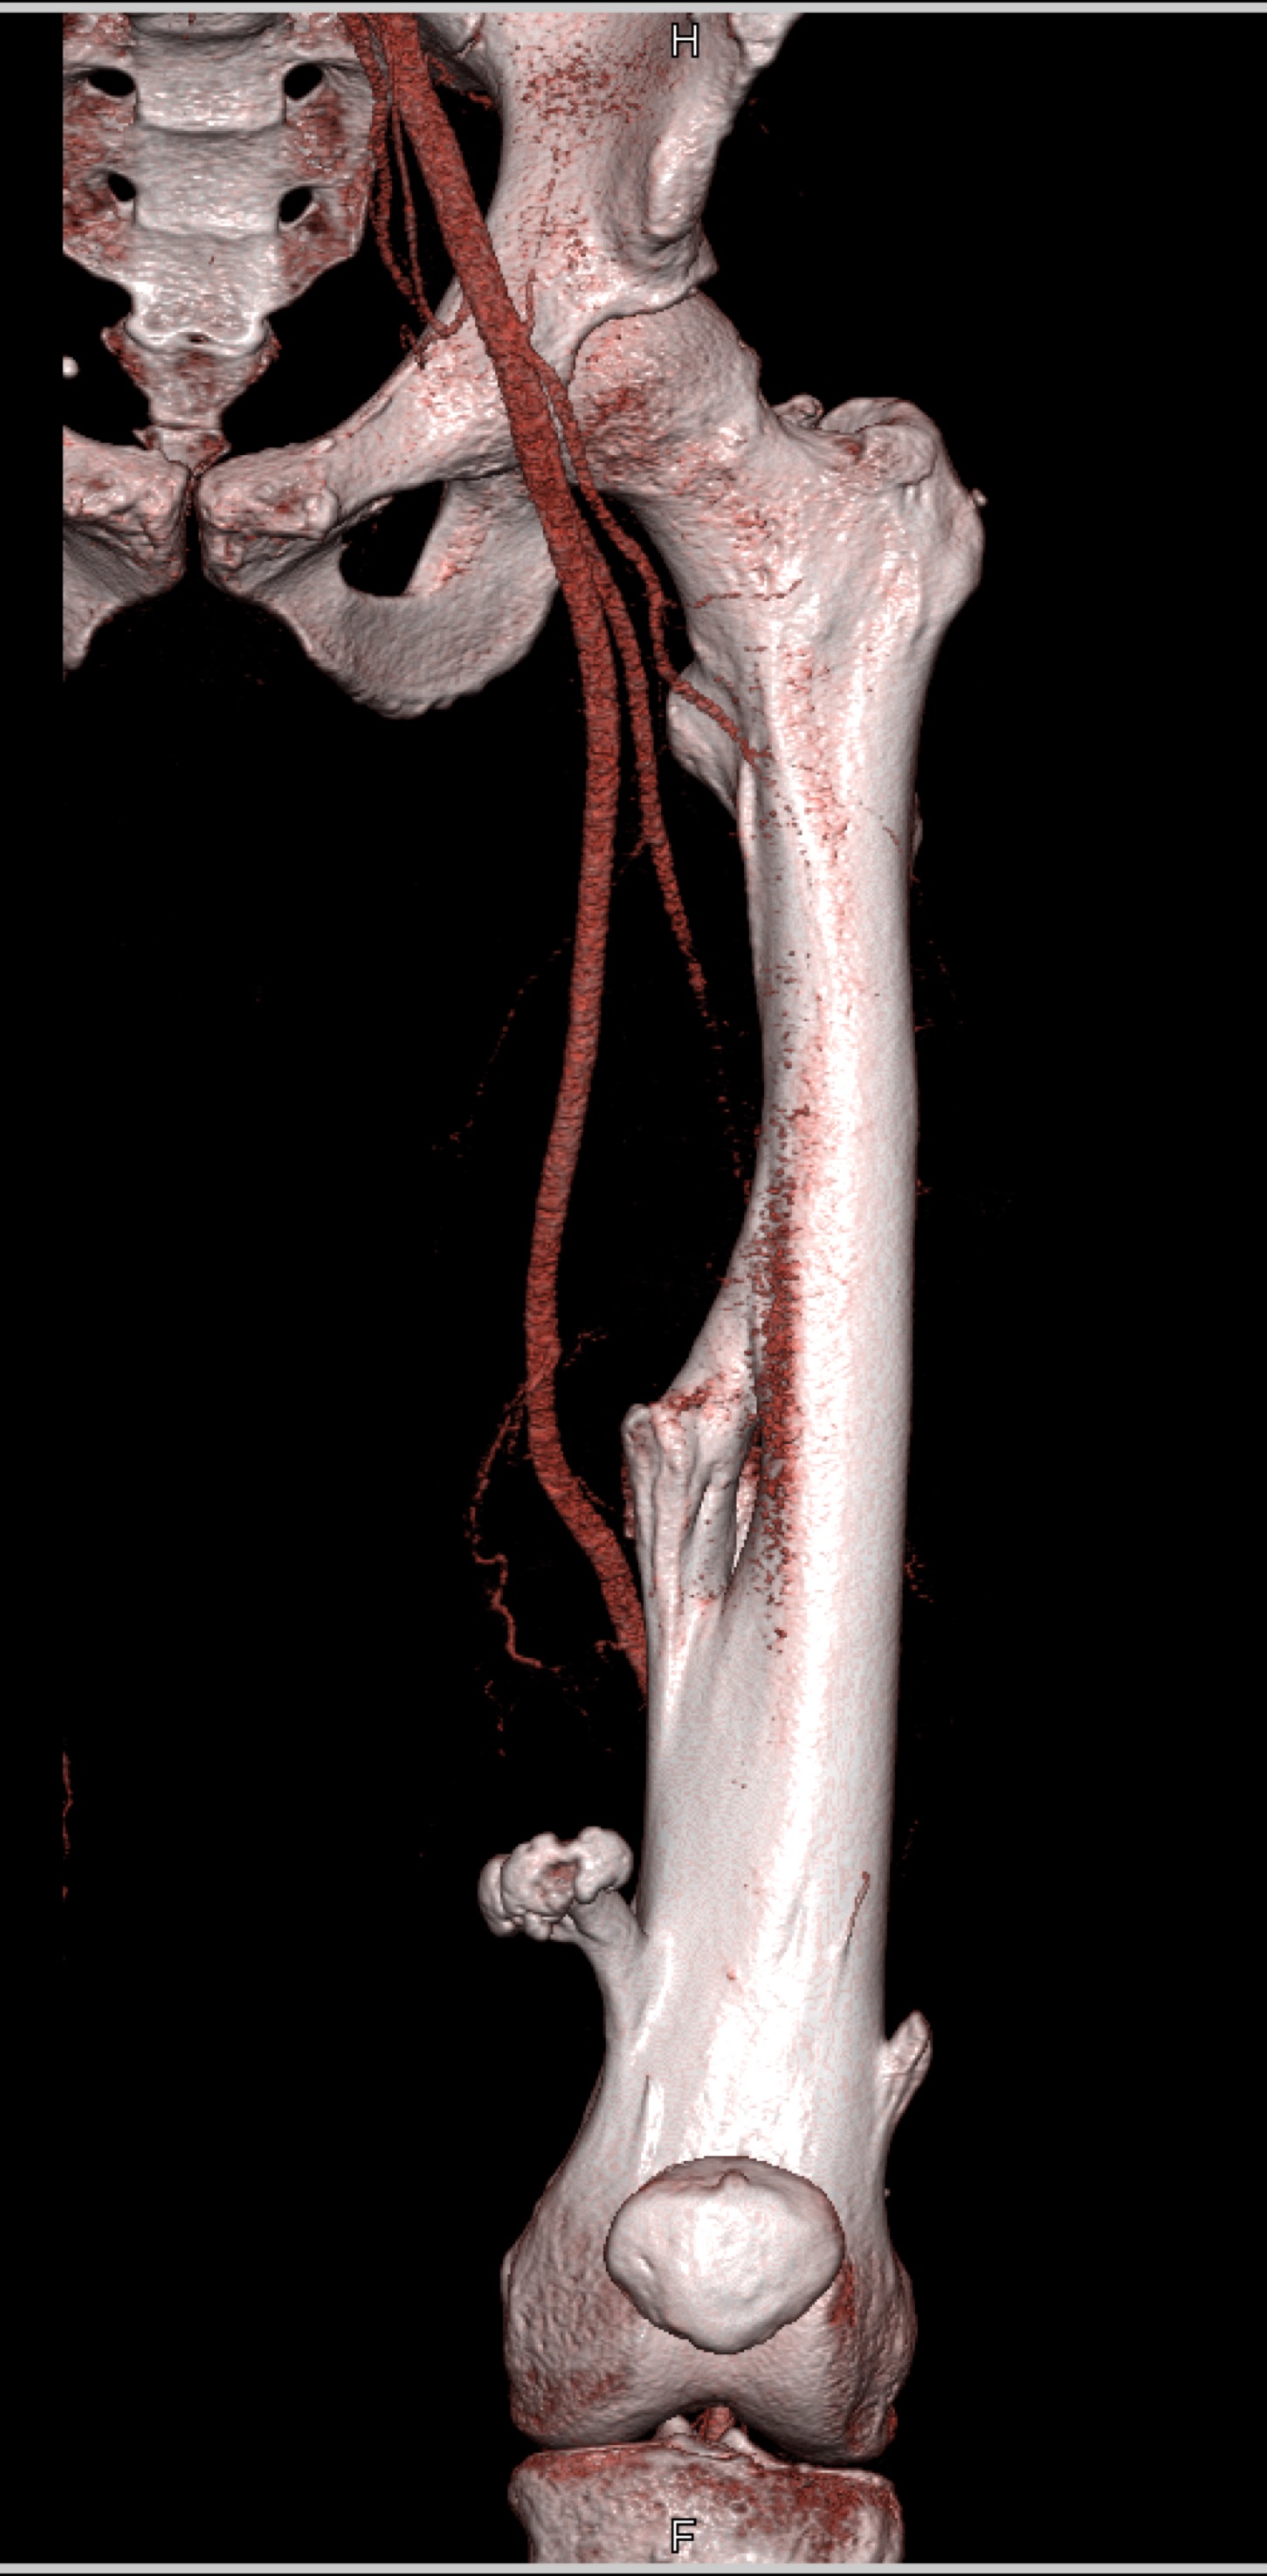

9) The most likely diagnosis in this case is?

healing femur fracture

exostosis femur compresses vessels

osteosarcoma

chondrosarcoma